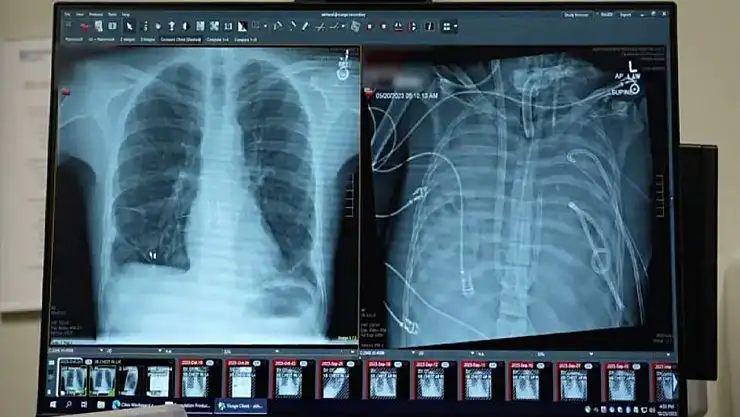

Bunun üzerine cerrahlar, hastanın hastalıklı akciğerlerini tamamen çıkararak geliştirdikleri yapay akciğer sistemine bağladı. Sistem, kalbin sağ tarafından alınan kanı bir pompadan geçirerek oksijen ekliyor ve karbondioksiti uzaklaştırıyor, ardından kanı kalbin sol tarafına yönlendirerek vücuda pompalanmasını sağlıyor. Böylece hem kalbin normal işlevi korunuyor hem de dokulara oksijen ulaştırılıyor.

Daha önce doktorlar, ekstrakorporeal membran oksijenasyonu (ECMO) adı verilen dış destek sistemini kullanarak, nakil bekleyen bazı hastaları akciğersiz olarak hayatta tutmuştu. Ancak Bharat, ECMO’nun kalp için yeterli kan akışını sağlamadığı için gerçek anlamda bir yapay akciğer olmadığını ifade etti.